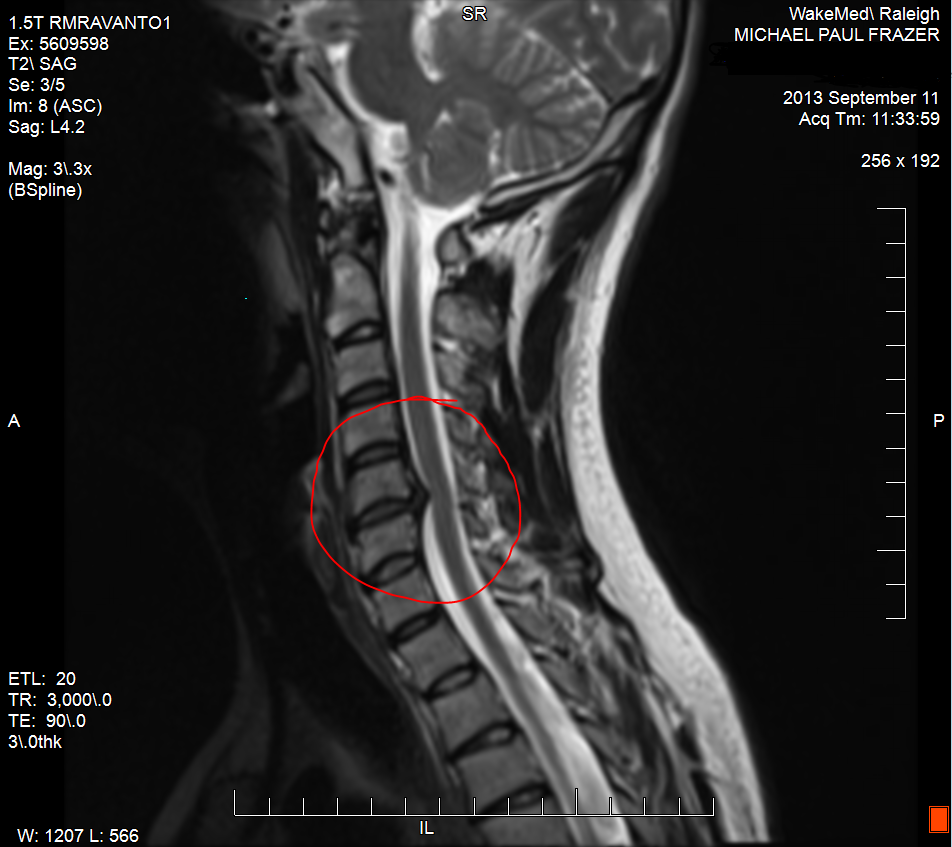

cervical degenerative spinal myelopathy